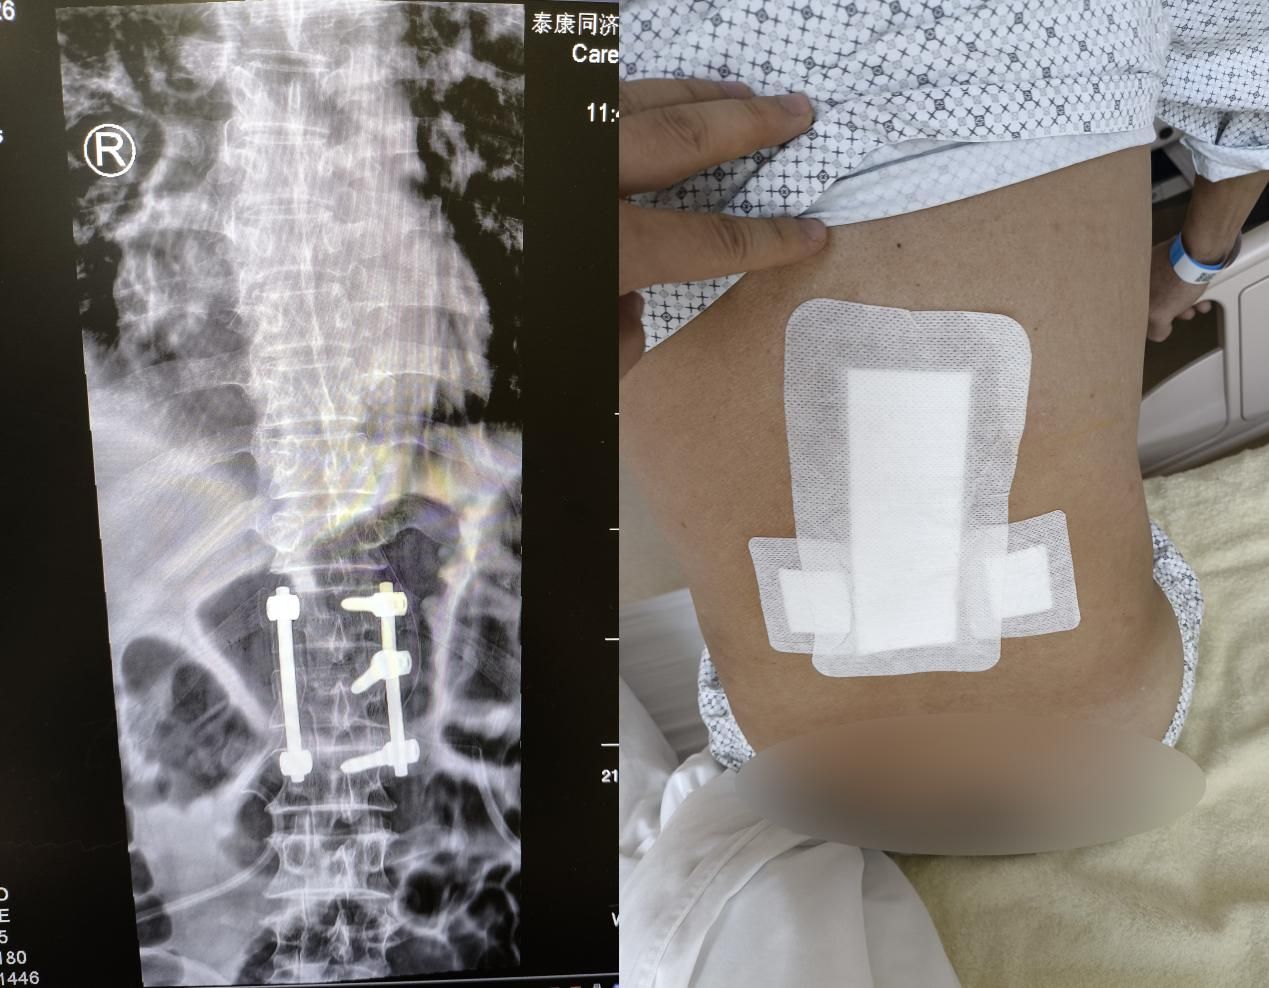

【長(zhǎng)江云】男子高處墜落致腰椎嚴(yán)重骨折 微創(chuàng)手術(shù)為家庭頂梁柱修好“頂梁柱”

男子高處墜落致腰椎嚴(yán)重骨折 微創(chuàng)手術(shù)為家庭頂梁柱修好。泰康同濟(jì)(武漢)醫(yī)院創(chuàng)傷外科團(tuán)隊(duì)成功為高處墜落致腰椎嚴(yán)重骨折的男性患者實(shí)施。肌間隙微創(chuàng)入路腰椎骨折切開(kāi)復(fù)位內(nèi)固定術(shù)。手術(shù)以極小創(chuàng)傷重建患者脊柱穩(wěn)定性。傳統(tǒng)開(kāi)放手術(shù)雖能...